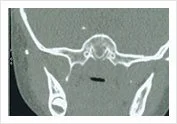

Enlarged obstructive adenoids may usually be associated with chronic sinusitis as the CT scan shows.

Adenoidal Hyperplasia Obstructing Upper Airway with associated sinusitis